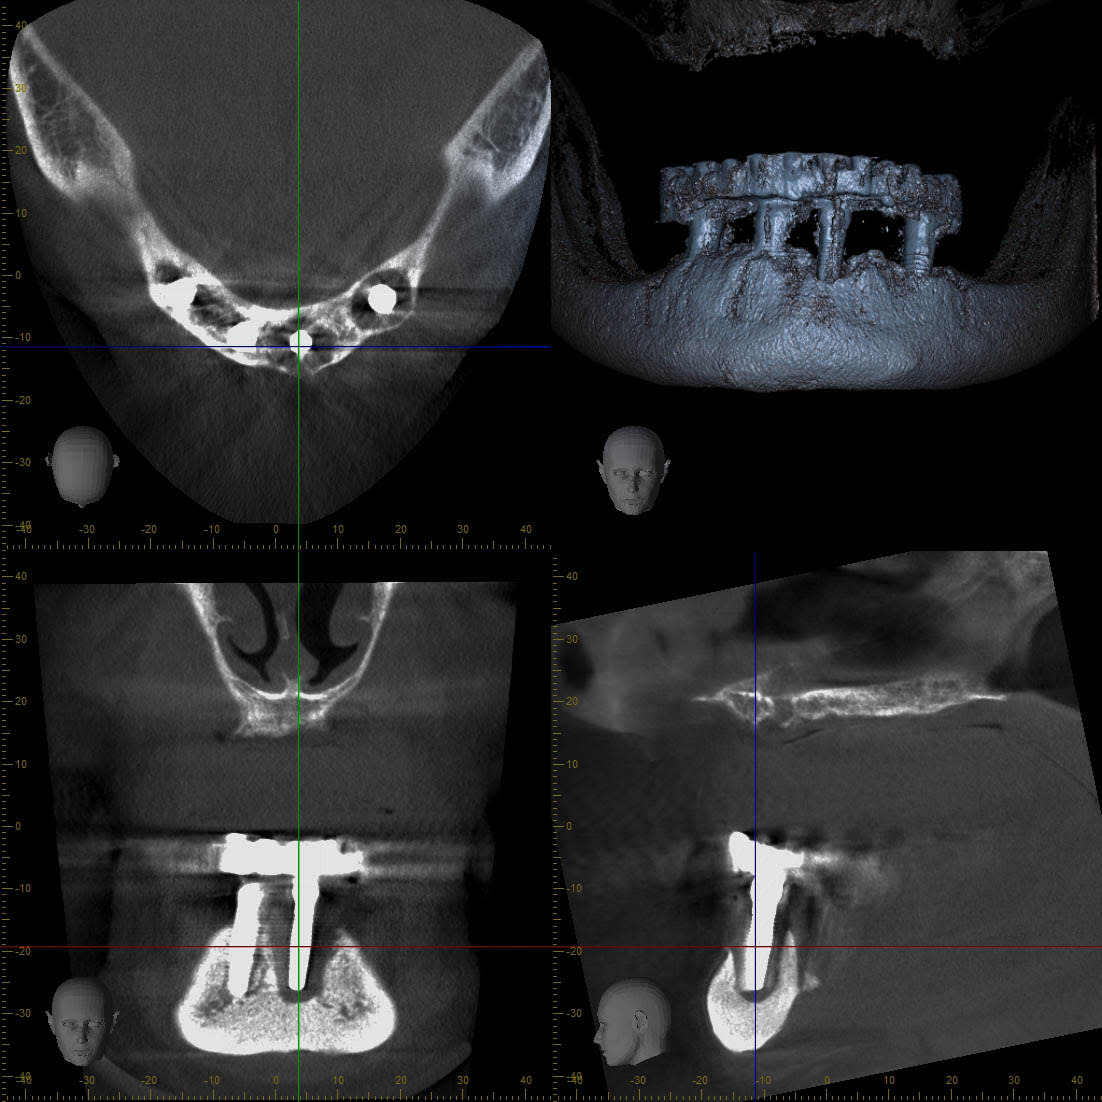

effectivement, c'est la chose la plus importante à gérer pour le moment.

je complète le cas;

82 ans

pose des implants par un praticien de Metz il y a10 ans. aucun problème particulier.

la prothèse venait d'être faite juste un peu avant le rachat du cabinet.

pratiquement aucune visites en 10 ans ...

la patiente est venue me consulter car elle souhaité la même chose au maxillaire. c'est là que j'ai découvert le pot aux roses il y a 3-4 semaines.

je lui ai dit que pour moi il était urgent de virer les implants et de prévoir une reconstitution osseuse au plus vite.

réponse de la patiente pas du tout motivé ( je peux le comprendre) ; après les grandes vacances, la communion du petit dernier, le voyage au Portugal, etc.... bref pas avant 5 mois...

elle a été prévenue du risque de casse.

au final, les vis ont cassées dans les piliers multi-unit vendredi dernier.

intervention pour retirer le kyste et curetage avec reconstruction osseuse par ROG ( bioos, membrane et tutti quanti..)

empreinte des piliers multi unit après avoir galéré pour retirer les vis cassées (d'où le coût plus élevé que si ça avait été fait avant)

repositionnement de la prothèse sur le modèle en plâtre pour retrouver la DV

réalisation d'un autre complet haut et bas avec DV et courbe occlusale convenable.

la suite dans quelques mois quand il y aura de l'os...

On peut remarquer la tres jolie expansion realisee par les kystes, certes en 10 ans mais tout en souplesse!